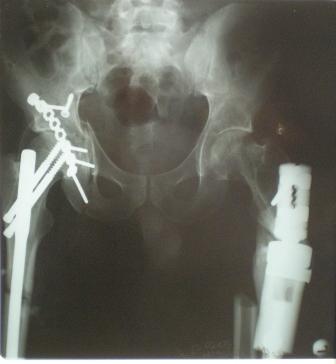

Уважаемые коллеги! Помогите пожалуйста в лечении сложного клинического случая Пациент 33 лет поступил 1.02.08 с диагнозом: Множественная травма. Т-образный перелом свода, перелом заднего края правой вертлужной впадины. Поперечный подвертельный перелом диафиза, подвздошный вывих правого бедра. Поперечный подвертельный перелом диафиза на фоне консолидированного косого перелома в\3 левого бедра в порочном положении. Открытый краевой перелом надколенника правого коленного сустава. Открытый оскольчатый перелом н\челюсти. Закрытый неосложненный перелом V ребра справа. В настоящее время больной компенсирован. Планируем: в положении больного на спине выполнить БИОС левого бедра ретроградно. После повернуть на левый бок и выполнить БИОС правого бедра антеградно одновременно с Y-образным доступом к вертлужной впадине. После - остеосинтез вертлужной впадины реконструктивными пластинами. Посоветуйте пожалуйста: 1. возможно ли выполнить все 3 операции одномоментно? 2. если возможно, то м\б начать операцию на стороне более тяжелого повреждения? Как при этом укладывать, и каким способом оперировать? 3. стоит ли выполнять БИОС левого бедра при условии, что если выбрать штифт длинной до б\вертела, то при введении проксимальный конец пройдет мимо б\вертела по задней поверхности?Заранее благодарен. Гринь Алексей.

Глубокоуважаемые коллеги! Благодарю за полезные советы, которые нам очень помогли в выборе оперативной тактики пациента. 13.02.08 мы выполнили первый этап оперативного лечения этого больного. Вначале зафиксировали левое бедро АВФ Гофмана

(главный травматолог области достал из каких-то «анналов», первый раз в жизни увидел этот аппарат в живую). После наложения «ДРУ Челнокова» выполнили ЗИО правого бедра реконструктивным штифтом Chm. Далее уложили пациента на левый бок и выполнили остеосинтез вертлужной впадины. Ограничились задне-латеральным доступом без отсечения вертела, чтобы не утяжелять операцию. Результат прилагается.